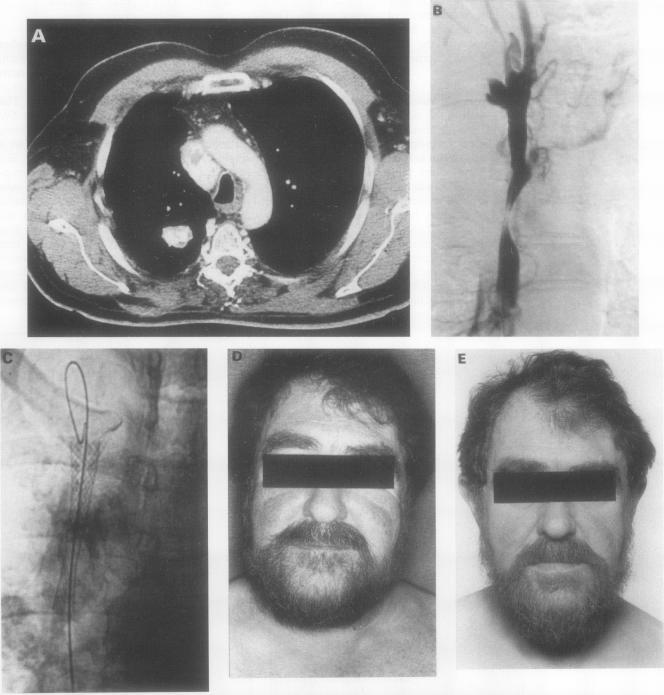

用于治疗上腔静脉阻塞的可扩张Wallstent支架。

Expandable Wallstent for the treatment of obstruction of the superior vena cava.

Palliative treatments for obstruction of the superior vena cava all have disadvantages. The use of a fine braided wire self expanding stent (Wallstent, Schneider (Europe) AG) in patients with malignant and benign causes of superior vena cava obstruction is reported.

METHODS

Five patients with obstruction of the superior vena cava were treated with balloon angioplasty of the stricture and the percutaneous insertion of an expandable Wallstent endoprosthesis across the site of the stricture. Four patients had advanced mediastinal malignancy previously treated by radiotherapy and one patient had fibrosing mediastinitis.

RESULTS

All patients experienced rapid symptomatic relief and, in three cases, complete palliation was achieved during survival times of seven weeks, nine weeks, and 24 weeks, respectively. Two surviving patients (with a recurrent thymoma and fibrosing mediastinitis) were free of symptoms when followed up at eight and nine months respectively.

CONCLUSIONS

Initial experience with the Wallstent endoprosthesis suggests that it is a valuable treatment alternative once conventional therapy has failed and gives rapid relief of symptoms to patients with obstruction of the superior vena cava.